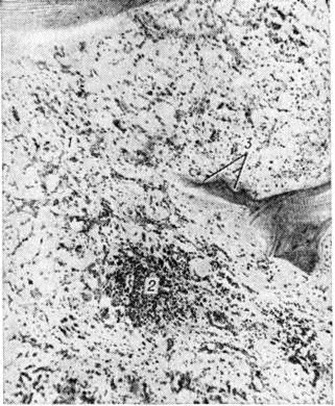

Рис. 10.

Микропрепарат костного мозга при остром лимфобластном лейкозе, протекающем с повторными ремиссиями: видны обширные поля жировых клеток (1), мелкие очаги лейкозной инфильтрации (2), истончение костной балки (3). Окраска гематоксилин-эозином; × 80.

В стадии полной ремиссии имеет место выраженное в различной мере восстановление деятельной кроветворной ткани, однако все же нередко обнаруживаются бластные клетки в виде мелких скоплений или одиночно расположенных элементов. При острых, а также хронический Лейкозы протекающих с повторными ремиссиями, часто имеется заметное увеличение жировых клеток (рисунок 10); в связи с длительным применением кортикостероидов нарастают процессы резорбции костного вещества, отражением чего является резкое истончение, а местами полное разрушение костных балок (рисунок 10). Эти изменения наиболее выражены при острых Лейкозы у детей и могут сопровождаться образованием известковых метастазов.